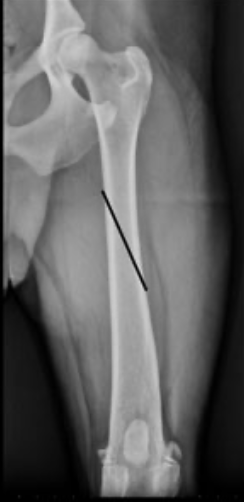

What type of fracture is this?

22

Q

A

short oblique